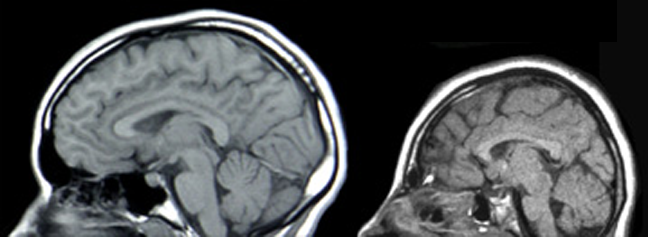

Microcephaly (left) vs. normocephaly (right)